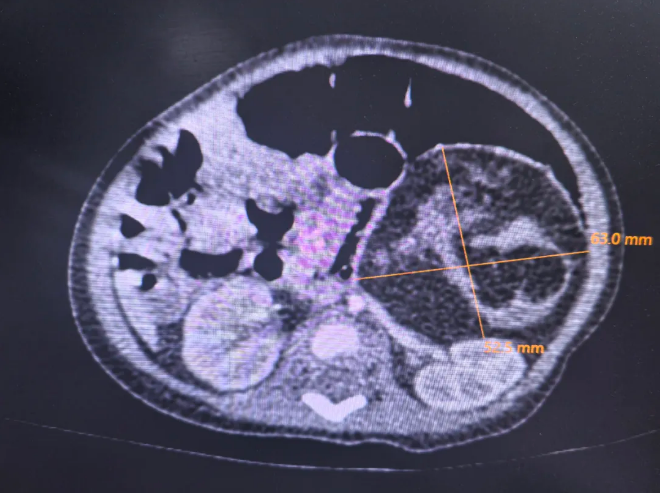

入院后,主管医生李景娜立刻为夕夕安排了检查,发现肿瘤已经增大到了6.0*5.2*4.7cm。王莹主任立刻组织了全科医生进行病例讨论。马立霜主任认为,瘤体生长迅速,且为实性瘤,与腹主动脉、下腔静脉等重要血管分界不清晰,术中存在大量出血可能。由于新生儿腹腔容积较小,瘤体占据大部分空间,不适合腹腔镜手术。最终经过多学科会诊决定为夕夕进行开腹手术。10月14日,夕夕的手术开始了。